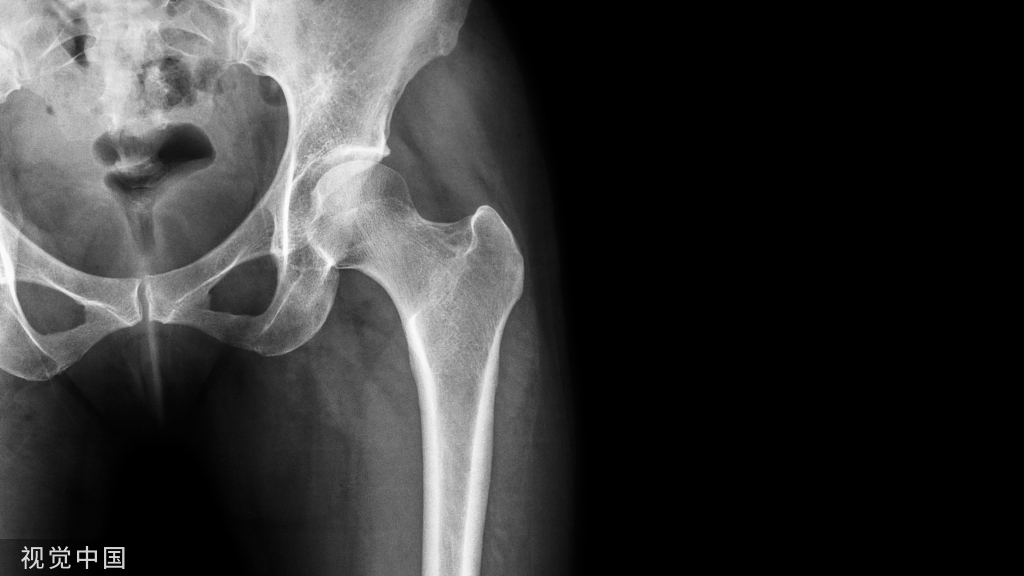

楔形骨折

对于楔形骨折(B3),按照AO基本理念,先以1-2枚拉力螺钉垂直骨折线进行加压。拉力螺钉可通过钢板,或不通过钢板。

再打钢板两末端锁定钉;再于骨折区两旁各打一枚保护螺钉(锁定钉)。保护螺钉与末端螺钉间视情况再各加打1-2枚锁定钉。仍需注意遵循长钢板、少螺钉的应力分散原则(如下图示)。